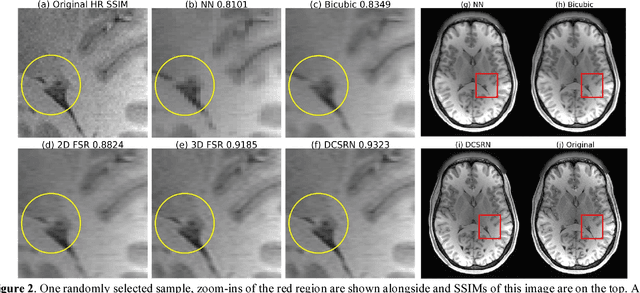

Abstract:Magnetic resonance image (MRI) in high spatial resolution provides detailed anatomical information and is often necessary for accurate quantitative analysis. However, high spatial resolution typically comes at the expense of longer scan time, less spatial coverage, and lower signal to noise ratio (SNR). Single Image Super-Resolution (SISR), a technique aimed to restore high-resolution (HR) details from one single low-resolution (LR) input image, has been improved dramatically by recent breakthroughs in deep learning. In this paper, we introduce a new neural network architecture, 3D Densely Connected Super-Resolution Networks (DCSRN) to restore HR features of structural brain MR images. Through experiments on a dataset with 1,113 subjects, we demonstrate that our network outperforms bicubic interpolation as well as other deep learning methods in restoring 4x resolution-reduced images.